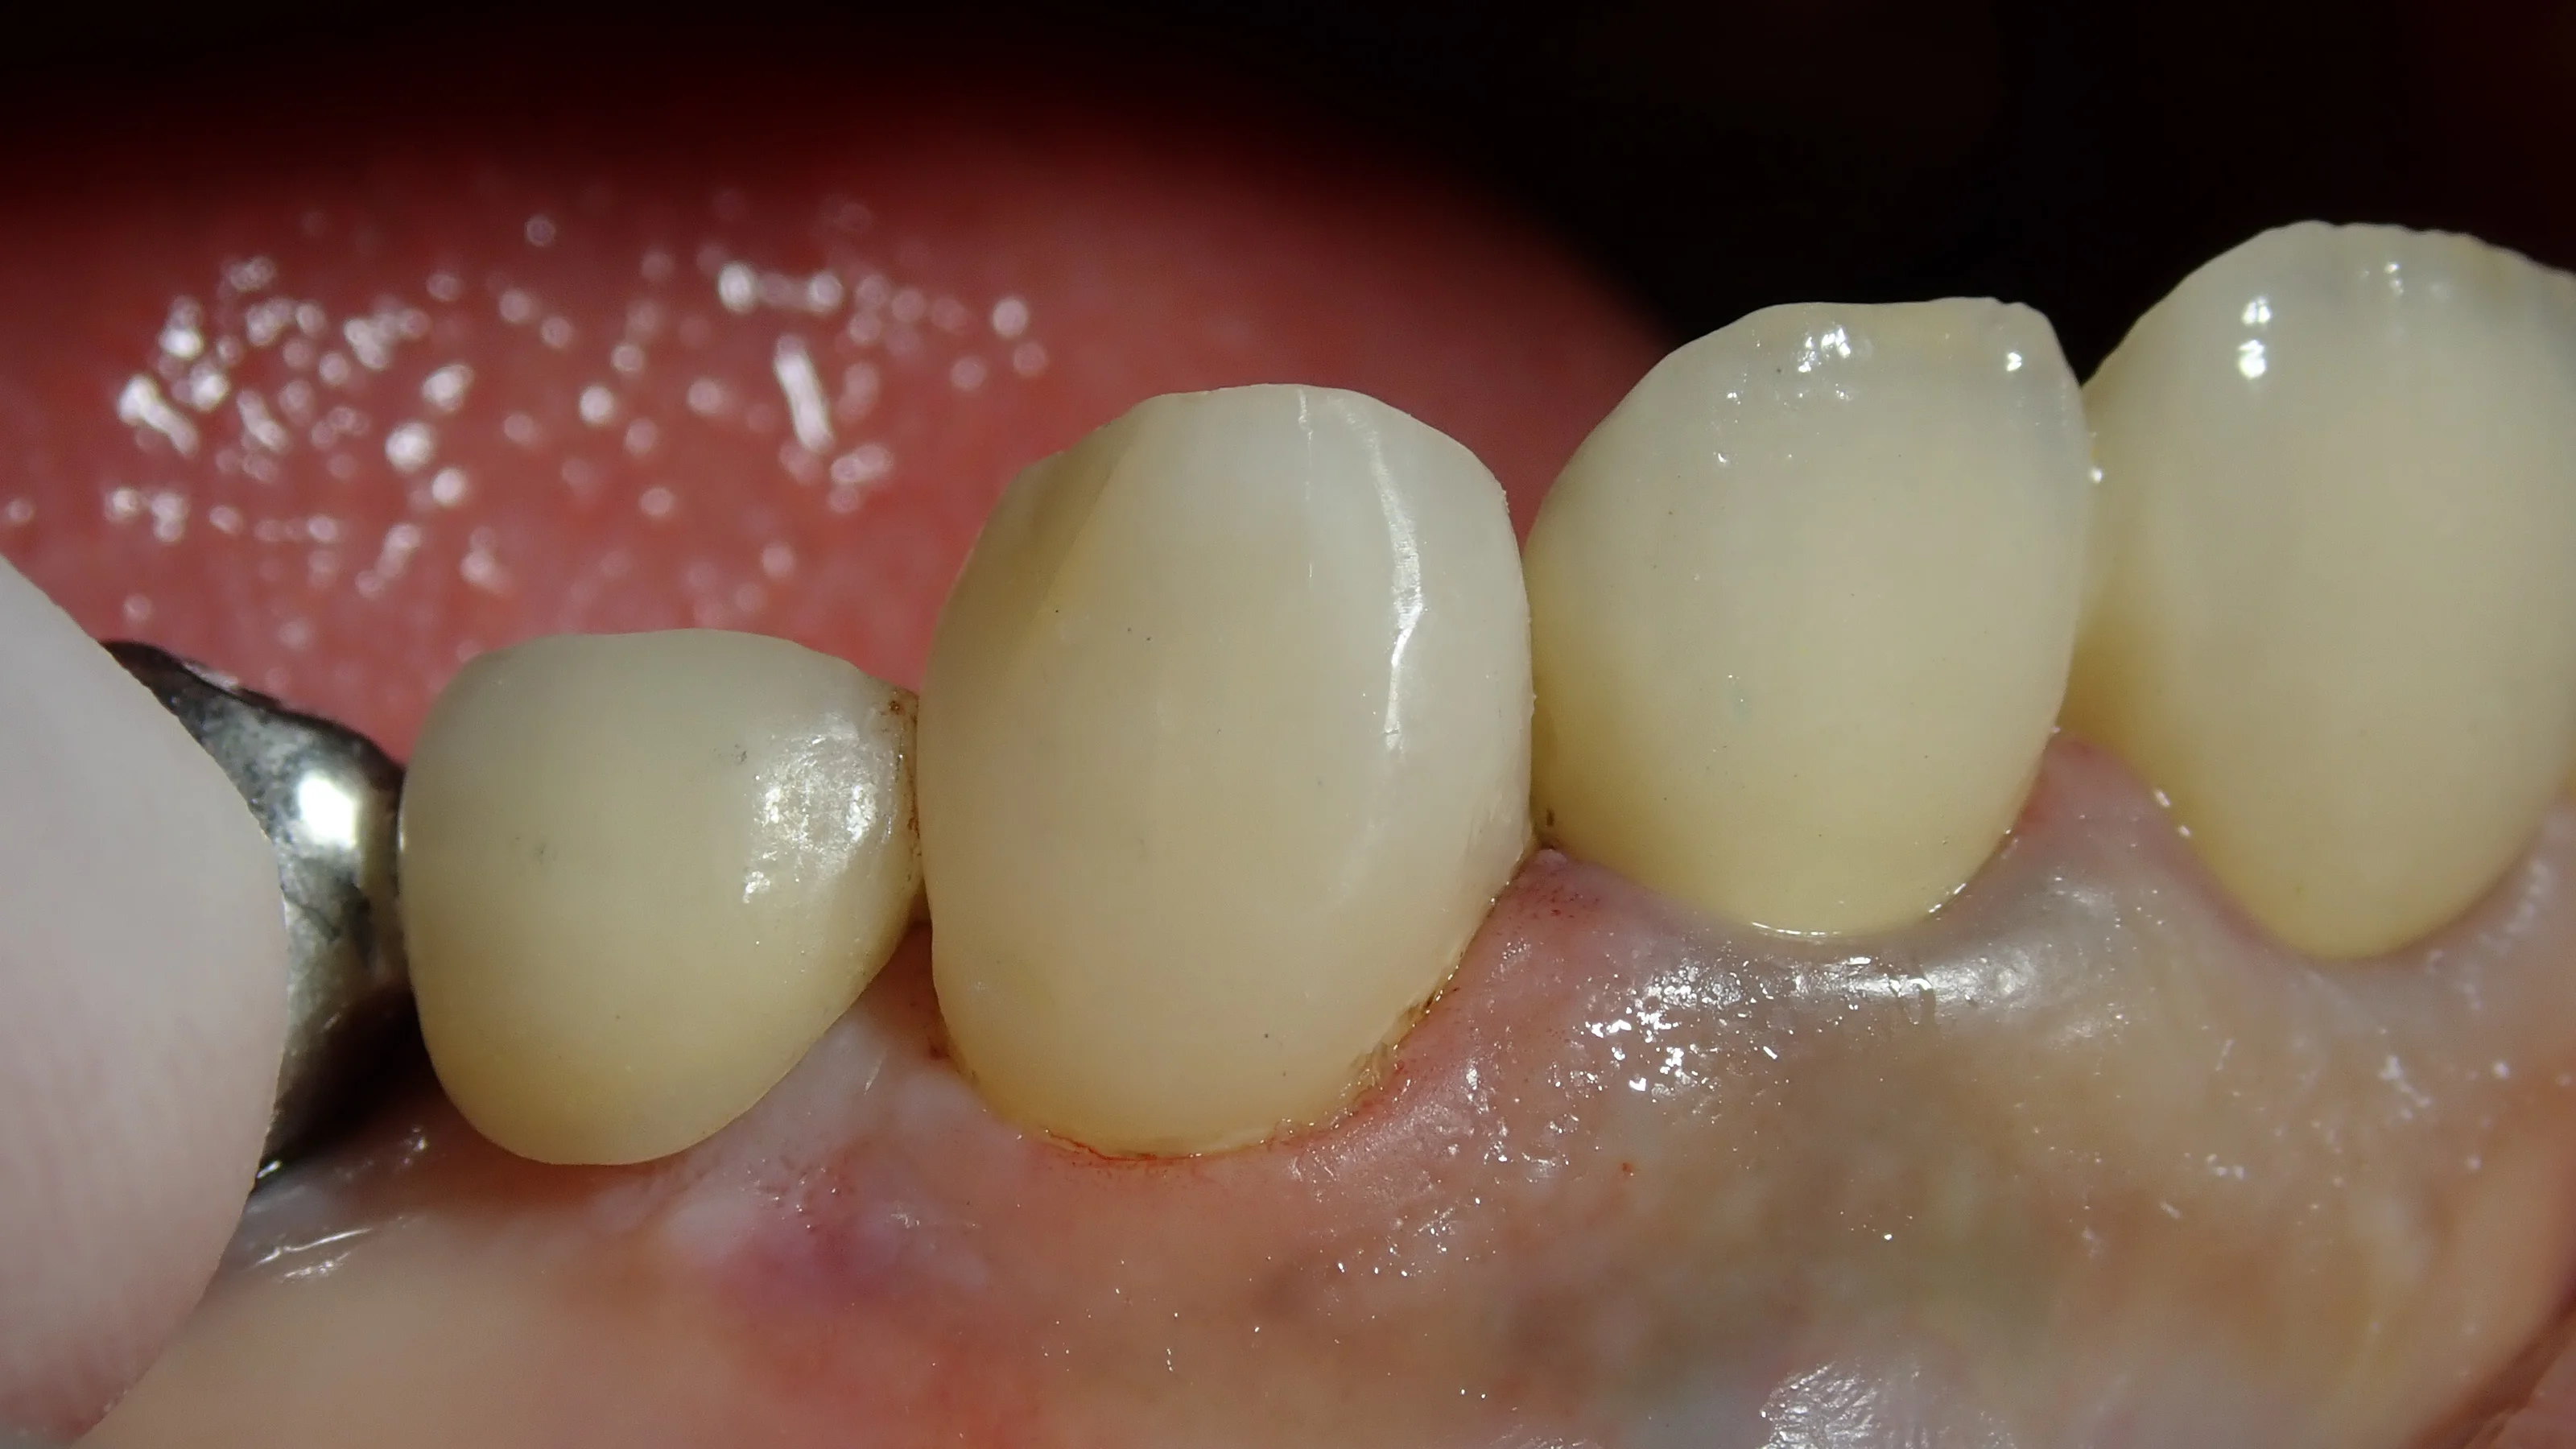

で、詰め終わったのがこちらです。

歯茎よりも深い所に虫歯が入ってしまっていたので、圧排糸と言って歯茎を押しのける糸を入れていたせいで、歯茎の一部が少し赤くなってしまっています。

この部分については2~3日程度で元に戻ってきますので、ご安心ください。

こんな感じで、最低限の歯質削除量で済ませることが出来るダイレクトボンディングは一押しの治療法です。